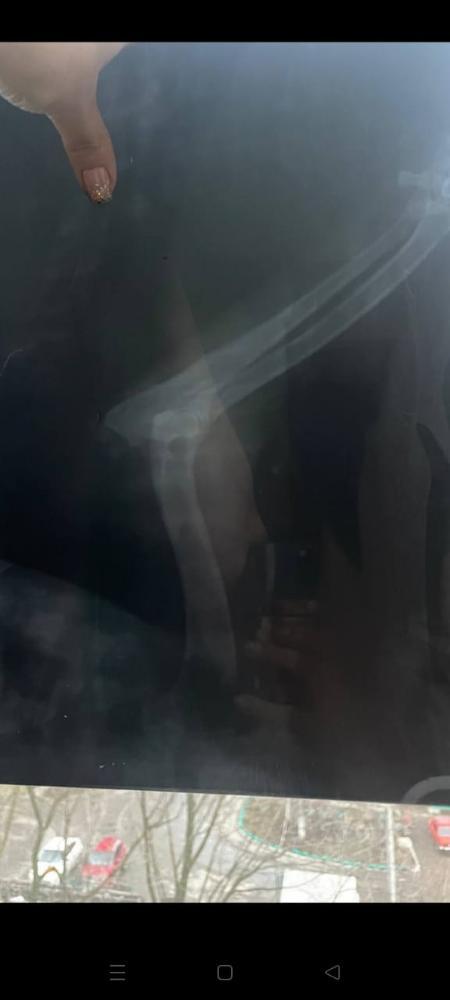

Кратко, нашли в январе 2024 , когда нашли не ходил, передняя лапа телепалась и шишка была на локте, не вставал на лапу, прокололи бонхарен, помогло. Сказали артроз.

Прикладываю старый рентген.